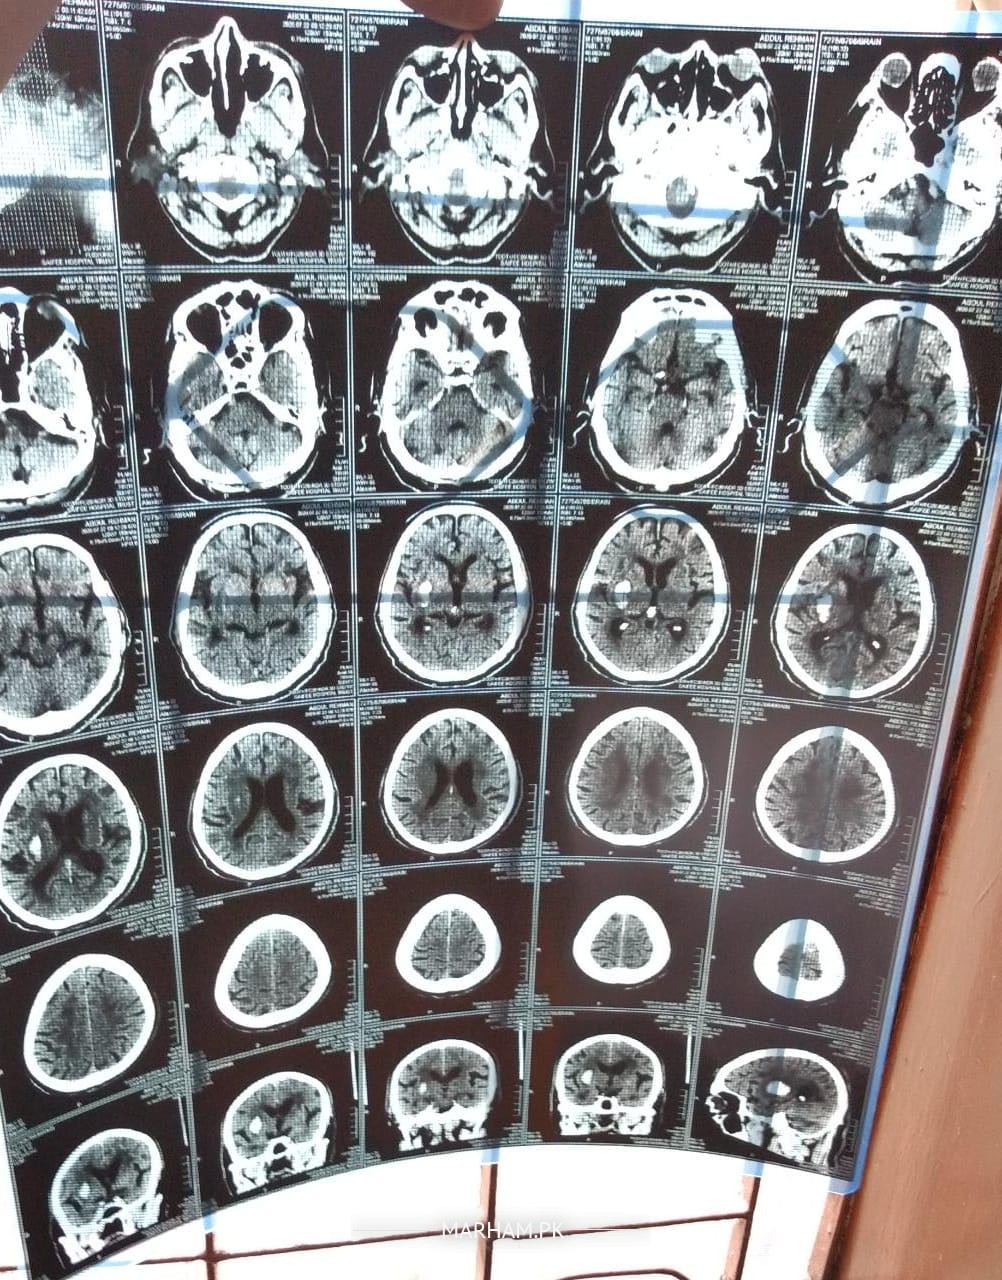

My father is severely depressed due to covid going on from past few months, lost interest in everything he would like to do earlier. He is a cardiac patient and had his cardiac bypass in 1995. He was very active entire life and never smoked or drank. Now from past few months he has stopped going out and 3/4 days ago he has stopped moving hisself from bed and says his left arm and leg is numb, we took him to hospital and got it checked his ECG, blood pressure and everything else was normal but in CT scan they found a white spot (attachment below) on right side of brain. He does feel his legs and arm now after 3rd he has stared moving his arm himself but complain pain in his left foot. In hospital they said it’s not stroke as they did come check up but they wanted to keep him in hospital for observation but they had only space in covid ward so they said we gonna put him on suspected covid patient my brother refused and brought him home. He is better but we are not sure what has happene

Also Sharing saifiee hospital report please check

Sorry for a late reply as i couldn’t receive ur msg due to some technical problems in the website. Hope your father is doing well. Well, according to the report there’s a possibility of stroke (falaj), and for further evaluation you may book an online appointment so that a detailed history can be taken and then medication can be given.

Saifiee report